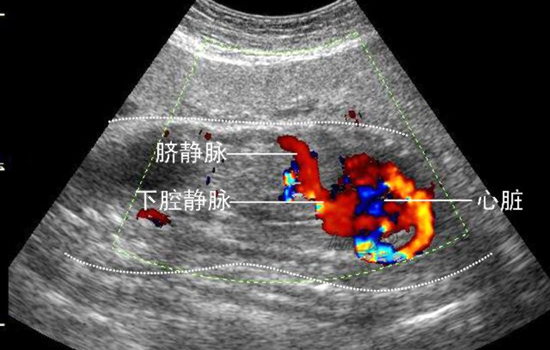

二维彩超能够观测到器官内部血液流动情况,彩超能够直观成像,显示更清晰,结果也更快速,在孕妇b超检查中有着非常大的作用。孕妇做检查是时候采用彩色b超检查,可发现异常血流,为诊断胎儿先天性心脏缺陷提供了诊断依据。

其实可以把普通b超和彩超归为一个范畴:普通b超就像黑白照片,彩色b超就是在b超的功能上多了一个彩色多普勒功能(CDFI),可以在黑白图像上看到彩色的血管,当彩色多普勒功关闭的情况下,它依然是黑白b超超声。